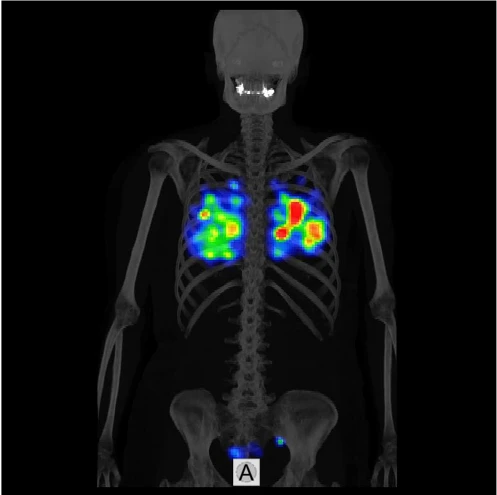

Это специализированное комбинированное устройство однофотонной эмиссионной компьютерной томографии/компьютерной томографии (ОФЭКТ/КТ) для осуществления различных томографических, кардиологических, онкологических и неврологических обследований. ОФЭКТ/КТ система ANYSCAN SC Mediso идеально подходит для 2D и 3D исследований и характеризуется большой производительностью и широким кругом решаемых проблем.

Совместное использование КТ и ОФЭКТ обеспечивает получение функциональной информации на молекулярном уровне и анатомической картины, с их последующим совмещением.